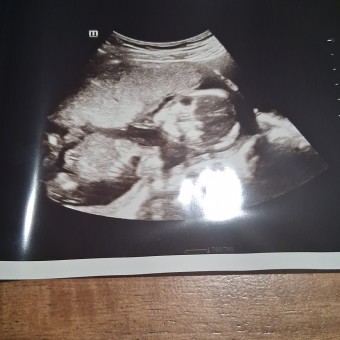

Elaine's Baby Registry

Elaine Vazquez & Brian Parker

Bartow, FL

July 20, 2026

Thank you for all your help and support with the preparations of our daughter's arrival❤️